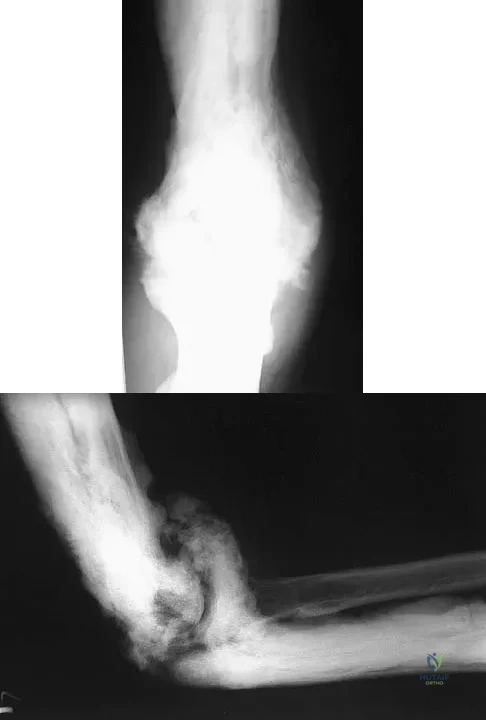

A 35-year-old man has atraumatic painless limited elbow motion. Radiographs are shown in Figures 33a and 33b. What is the most likely diagnosis?

A 65-year-old woman has had chronic aching discomfort involving her elbow for the past 6 months. Radiographs and a biopsy specimen are shown in Figures 38a through 38c. What is the most likely diagnosis?